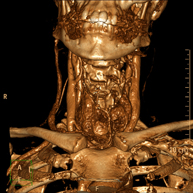

- Neck CT

Radiological test that provides high definition anatomical images of the neck using CT (Computed Tomography) equipment. Indicated for: thyroid study, control of treated tumours, study of lymph nodes, infections and abscesses.